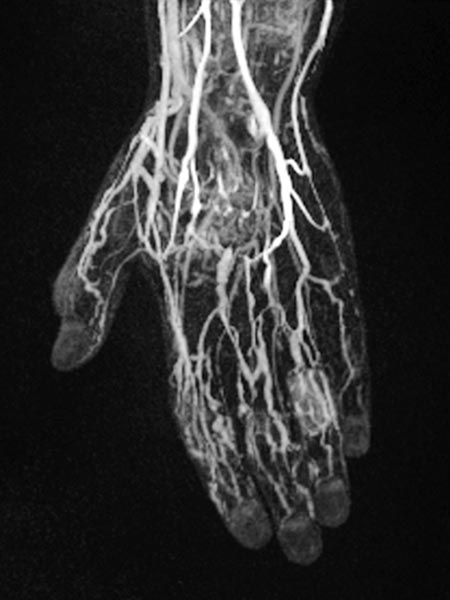

Dynamic, contrast-enhanced MR angiography of the hand, 30 s after intravenous contrast injection.

Normal hand arteries, no fast-flow situation, no dilated arteries or arteriovenous shunts are demonstrated.

Dynamic, contrast-enhanced MR angiography of the hand, 35 s after contrast injection.

Already in this early arterial phase, first enhancement of parts of the malformation via small arteriovenous fistulas (AVF) mainly in thumb, index finger and ring finger.

Dynamic, contrast-enhanced MR angiography of the hand, 67 s after contrast injection.

In this venous phase, slow pooling of contrast within the venous malformation.